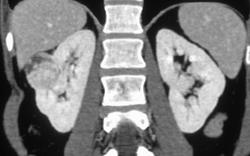

Vascular Renal Cell Carcinoma